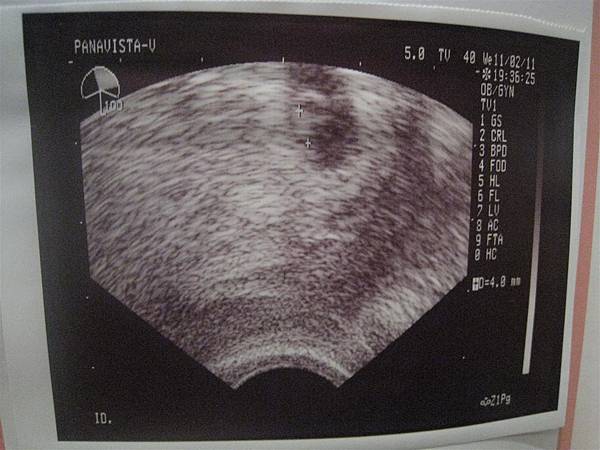

100.11.02 到新莊樂寶兒找黃光大醫生報到,看到小小胚胎了